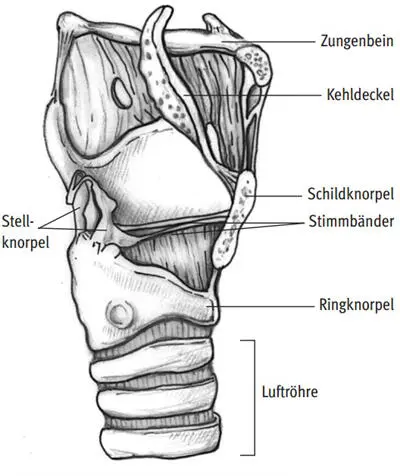

Abb. I.56: Kehlkopf mit Luftröhre

Teilweise Verschlüsse der Stimmlippen können auch regelhaft bei Bläsern während des Spielens beobachtet werden. Eine Beschreibung der bei den verschiedenen Blasinstrumenten im Kehlkopf ablaufenden Vorgänge findet sich in Kap. I.1.3, S. 49 ff.